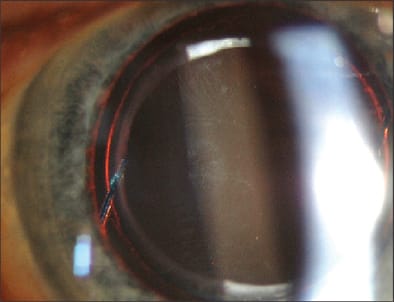

In addition to PCO, the IOL can opacify. The pathogenesis of IOL opacification is undetermined, with speculation that ultraviolet (UV) light is a contributory factor. Idiopathic brown opacification of IOLs (Figure 2) has also been reported.13-15 Glistening within some acrylic IOLs may be due to temperature-induced fluid formation in the optic related to Wagon Wheel and AcryPak packaging.16-19 Late opacification of hydrophilic IOLs can be particularly problematic.20-22

Figure 3. Brown discoloration of a multipiece multifocal hydrophobic acrylic posterior chamber intraocular lens.